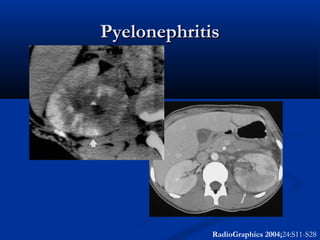

Contrast

 Wedges of hypoattenuation (edema, obstruction, and vasospasm)

 Dense on delayed

 Striations (focal, diffuse)

Pyelonephritis



DDX

PN

Recent stone passage

Non-stone obstruction (clot,

fungus ball, iodinovir)

Acute vascular lesion (RA, RV

occlusion)

So, non-contrast findings

nonspecific.

Clinical exam/UA/hydro should

allow distinction

Consider contrast if unclear

RadioGraphics 2004;24:S11-S28